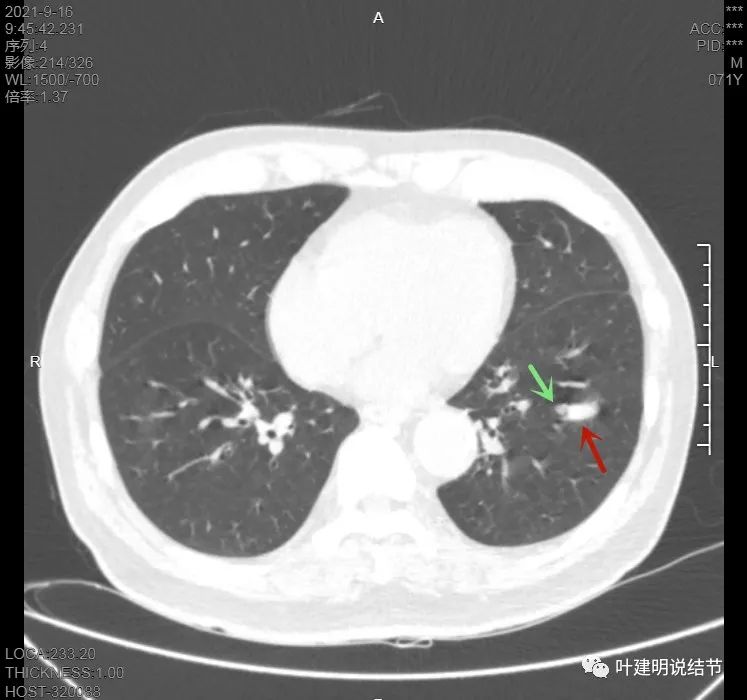

上图也示病灶是两个的,小的与大的之间有间隙的。大的病灶呈长方形似的

上图见主病灶长方形,边缘平直且光滑,没有毛刺、分叶或胸膜牵拉,粉色箭头示小病灶,在主病灶边上